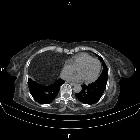

Morgagni-Hernie

Morgagni hernias (alternative plural: herniae) are one of the congenital diaphragmatic hernias (CDHs), and are characterized by herniation through the foramen of Morgagni. When compared to Bochdalek hernias, Morgagni hernias tend to be:

Morgagni hernias most often contain omental fat, but transverse colon (60%) or stomach (12%) may be included within the hernia.